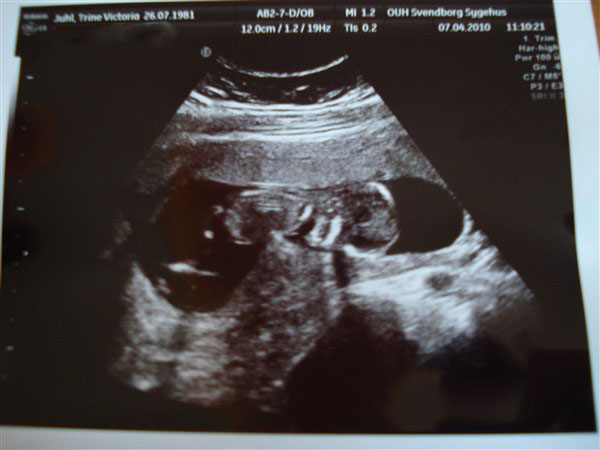

okay! så jeg lagde mig på briksen og fik trukket temmelig godt ned i bukserne og en ordentlig klat "smør" på maven og DER lå vores baby

babyen spjættede og rullede og tørrede sig i øjnene på præcis samme måde som August (vores kat) og slog ud med armene og hoppede med numsen - det ER en rumpenisse, der var godt gang i bagen på den

og lige på det første billede kunne vi allesammen med det blotte øje se, at nakkefolden var meget meget tynd. men så blev lægen så ivrig efter at vise os hvor fin den var, at han glemte at tage billede, så han måtte scanne og scanne og scanne og jeg måtte flere gange løfte bækkenet og vrikke med måsen og til sidst kom sygeplejersken og forsøgte og så fik de den endelig målt. da de så havde tastet alt ind i systemet udbrød de begge to "ja, det er meget, meget lavt!" og smilede over hele femøren. "din termin bliver rykket til 13. oktober (på Carlas fødselsdag) og din baby har det rigtig godt, tallet er 1:15000, det er en meget meget meget lille risiko"

I får lige et par snapshots, den ligger ligesom på maven med hovedet ude til venstre: